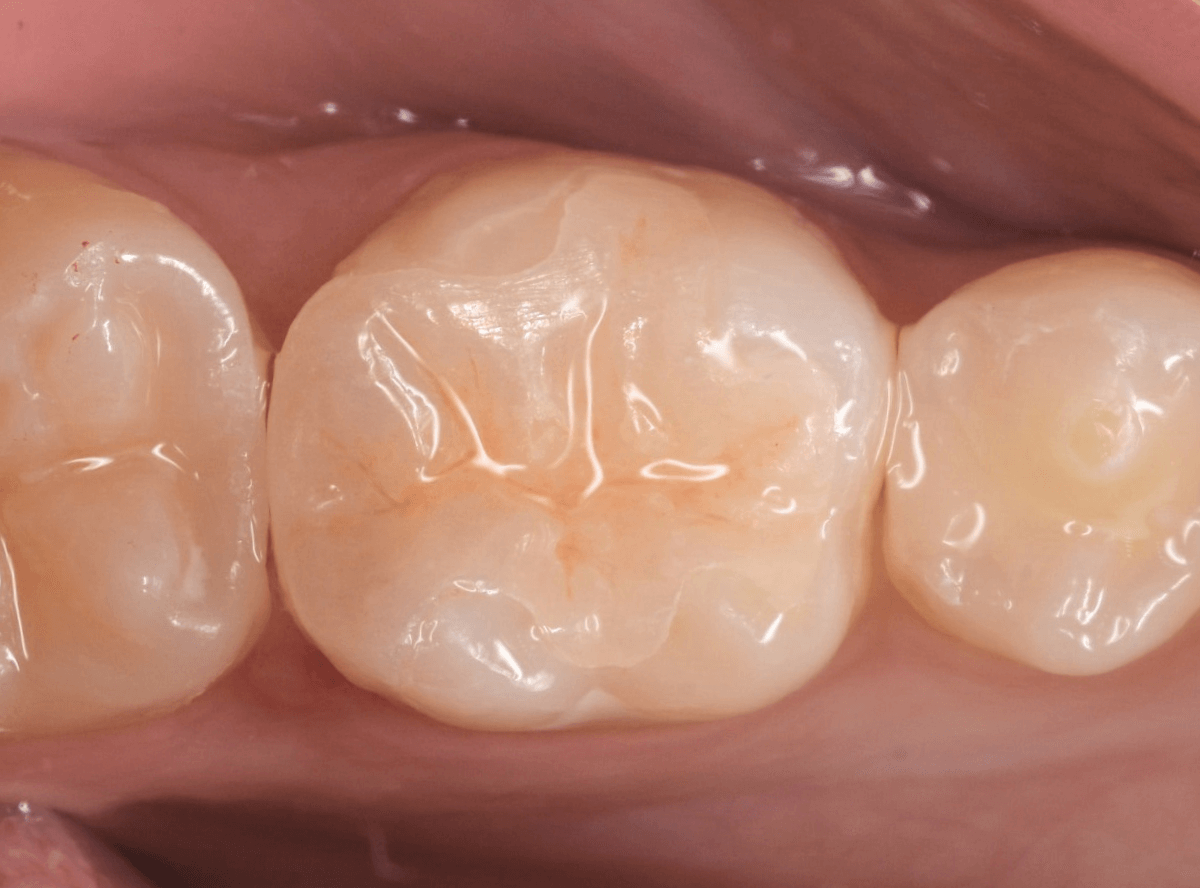

治療後の状態です。

ジルコニア・インレーはE-MAX・インレーより審美性に劣るのですが、患者さんにもご満足いただける仕上がりになり、ホッとしました。